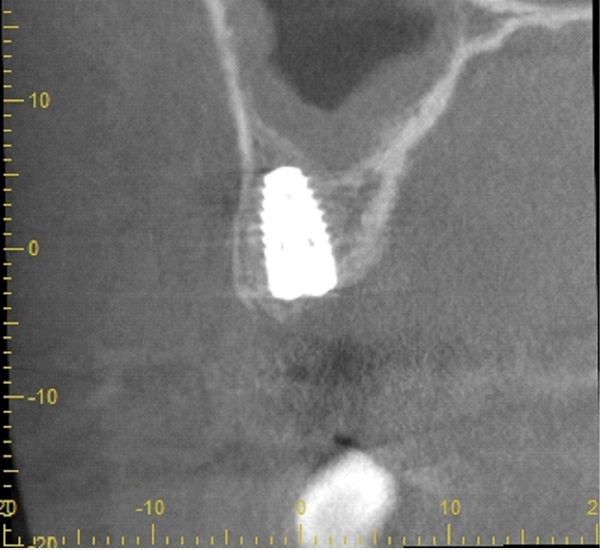

| 年代・性別 | 50代 男性 |

|---|---|

| 主訴 | 前医で前歯を抜かなければならないがインプラントはできないと言われた |

| 治療期間 | 約12ヶ月 |

| 費用 | 600,000円 |

| 治療内容 | インプラント、骨造成、結合組織移植、セラミック修復 |

| 治療に伴うリスク | インプラント周囲炎 セラミックの破折、脱離 |